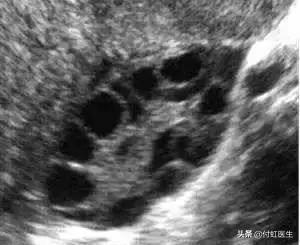

3. B超:临床医生可以通过超声检测卵巢体积、基础窦卵泡数目(AFC)、卵巢动脉血流来评估卵巢储备功能,其中基础状态(月经第2~3天)的卵巢体积变小与卵巢储备的原始卵泡减少、卵泡生长的数目少有关。

窦卵泡数AFC减少,窦卵泡指早卵泡期直径2~9mm的卵泡,通常认为双侧卵巢窦卵泡数合计少于5~7个提示卵巢储备功能下降。

对于涓涓2次化验FSH轻度升高的情况,付虹医生目前的带教老师刘教授建议她再做盆腔B超检查一下窦卵泡数AFC,以及基础抗苗勒管激素(AMH)水平,综合判断卵巢功能。

做B超检查我们看到,涓涓的窦卵泡数AFC,左侧卵巢4-6mm的卵泡10个,右侧卵巢4-6mm的卵泡8个,属于正常状态。